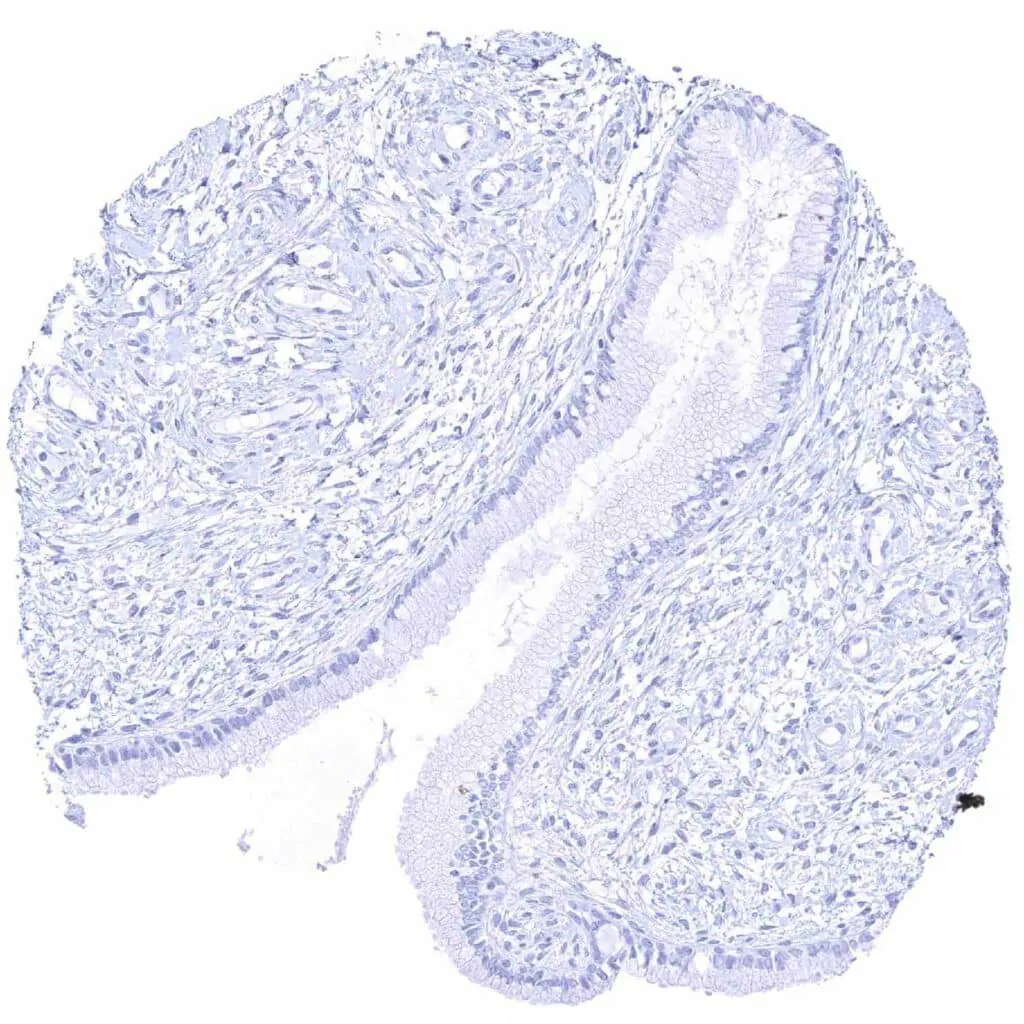

Rectum, mucosa